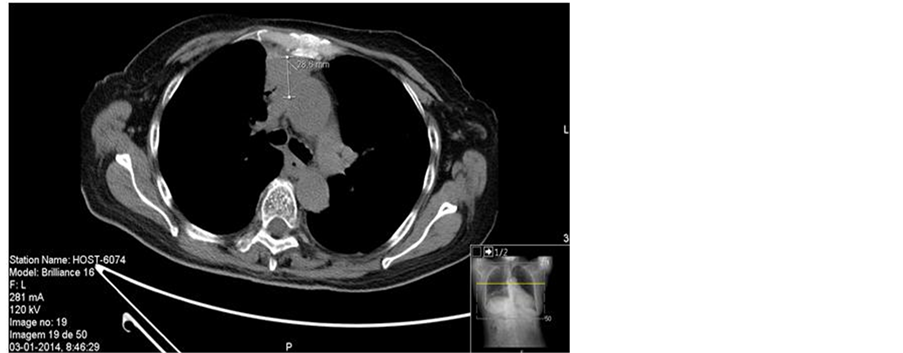

Thoracic computed tomography (CT) scans showed a heterogeneous anterior mediastinal lesion with areas of central necrosis, necrotic nodular lesion of the pleura in relation to the right costophrenic angle and significant pericardial effusion. It also presented with extensive areas of lung consolidation with air bronchogram compatible with bilateral basal pneumonia and associated parapneumonic left pleural effusion (Figure 2).

Figure 2. (a) Thoracic computed tomography revealed significant pericardial effusion (arrows); (b) (c) Thoracic computed tomography showed a nodular mass measuring 28.6 × 25.5 mm, with irregular borders in the anterior mediastinum, heterogeneous density, areas of coarse calcification and central areas of necrosis at its lower strand located in the right cardiophrenic angle.